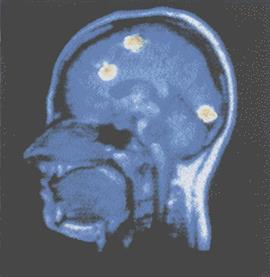

На изображении, полученном с помощью ПЭТ, видны три зоны в левом полушарии, активные во время решения речевой задачи.

Красным цветом показаны зоны с наибольшей активностью, синим — с наименьшей.